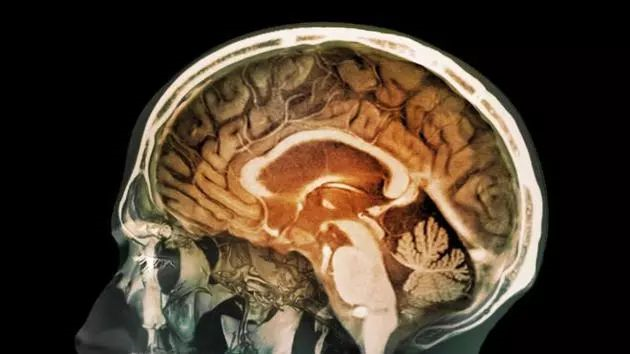

儿童的血脑屏障更容易被穿越,因此科学家们对儿童受到的影响感到愈加担忧。一些研究人员开始使用核磁共振扫描分析这些污染物对神经发育造成的影响,结果显示,大脑中的确发生了一些变化。

研究人员分析了145名12岁儿童的大脑核磁共振扫描结果,并利用住址信息估测他们接触到的污染程度,包括细颗粒物等,在分析中还考虑了人口统计学因素,确保社会经济状况和种族等因素与这些影响无关。

在比较了这些儿童近期接触的交通空气污染水平、焦虑症状、以及大脑成像信息后,该团队发现,污染暴露程度较高的儿童所报告的一般焦虑症状也更多,而在这些症状更严重的儿童大脑中,负责情绪处理的前扣带皮层中的肌醇含量较高,正常大脑中也含有肌醇,但肌醇水平异常往往与大脑病变有关。